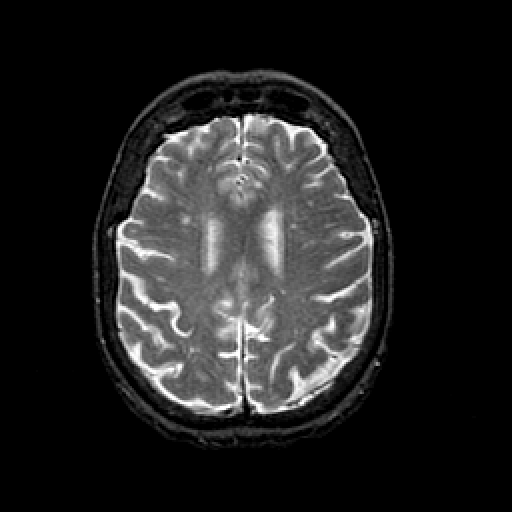

T2-weighted structural MR: Slice 36

Slice 36